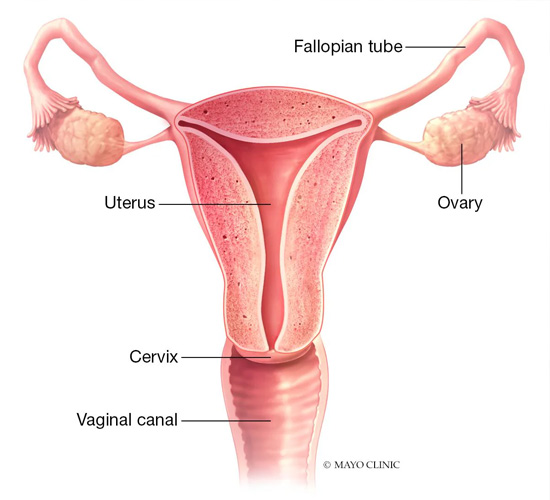

IUI

IUI is a simple, non-invasive fertility treatment where processed sperm is directly placed into the uterus, increasing the chances of conception.

Female Infertility

We diagnose and treat female infertility caused by hormonal imbalances, PCOS, endometriosis, and other reproductive issues with personalized fertility solutions.

Hysteroscopy

Hysteroscopy is a minimally invasive procedure used to diagnose and treat uterine conditions, improving fertility and overall reproductive health.

Laparoscopy

Laparoscopy is a keyhole surgical procedure used to diagnose and treat infertility-related conditions like endometriosis, fibroids, and ovarian cysts.

Uterine Fibroids Treatment

We offer advanced treatments for uterine fibroids, relieving symptoms and improving fertility through medication, minimally invasive procedures, or surgery.

Endometriosis Treatment

Specialized endometriosis treatments help manage pain, improve fertility, and restore reproductive health through medication, surgery, or hormonal therapy.